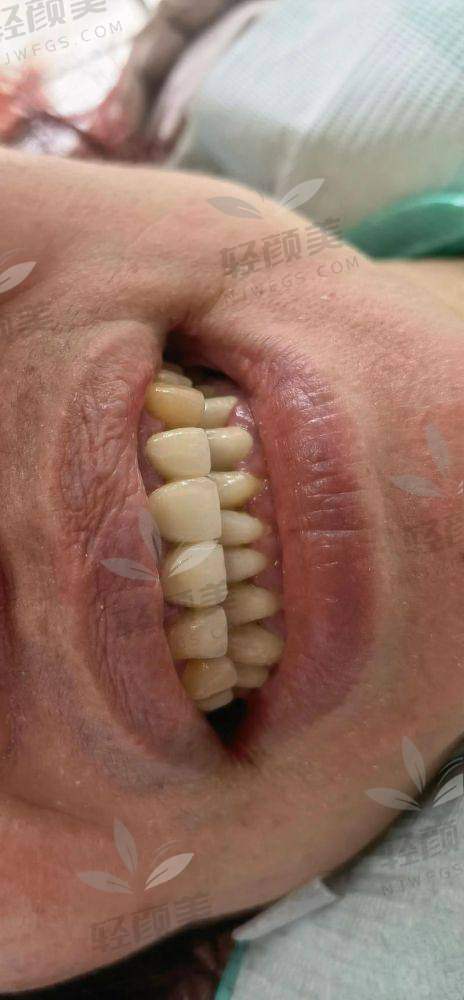

通俗点说,烤瓷牙=外表好看+内心强悍。它是一种戴在打磨过的牙齿上的牙冠,底下是金属或氧化锆、玻璃陶瓷,上面包着一层陶瓷。功能上,它既能弥补蛀牙、裂牙、缺失,也能改善牙齿颜色和形态。比树脂补牙更结实,同时容貌还在线,拍照都能看到牙齿在发光✨。

而且关键是:靠谱的烤瓷牙,能用8-15年甚至更久!所以别光看脸,那些贵点的材料是真的更抗剐蹭、不过敏、更贴合真牙!

烤瓷牙分为“金属烤瓷”和“全瓷烤瓷”,前者经济实用,后者主打自然美学和生物兼容性。直接上榜单,让你少走弯路?